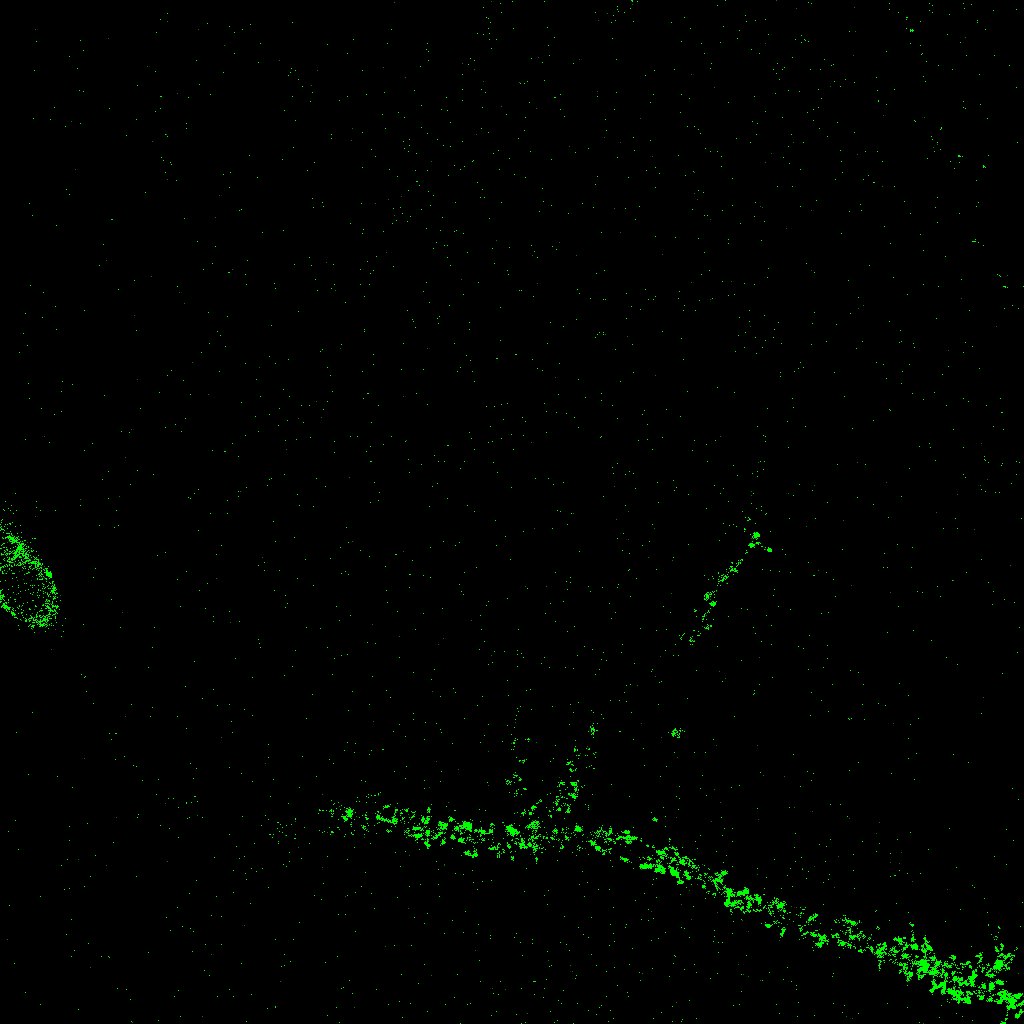

Por último, se ha planteado también el problema de la localización de la estructura de una neurona a partir de una pila de imágenes. Partiendo de una serie de imágenes 2D correspondientes a distintas alturas (figura 5, en este caso de tamaño 1024×1024102410241024\times 1024 píxeles o 49×49494949\times 49 micras), se trata de realizar la reconstrucción 3D determinando la estructura de la neurona y descartando otros elementos irrelevantes.

Refer to captionRefer to captionRefer to captionRefer to captionRefer to captionRefer to captionRefer to captionRefer to caption

Figura 5: Pila de imágenes en distintos niveles

Las imágenes neuronales obtenidas en el microscopio confocal proporcionan una pila de imágenes 2D correspondientes a diferentes alturas. A partir de ellas, calculamos la proyección máxima y una filtración sobre ella. La homología persistente de la filtración calculada permite determinar las neuronas que aparecen en la imagen y desechar el ruido.

Como una generalización de la noción de homología persistente ha surgido también el concepto de persistencia zigzag [4]. En este caso no hace falta construir una filtración por lo que podemos utilizar directamente las imágenes 2D obtenidas del microscopio. La persistencia zigzag nos da la relación entre ellas y nos permite también determinar la estructura de las neuronas presentes en la imagen estudiada.

El plugin NeuronPersistentJ [14] se utiliza para detectar la estructura de una neurona a partir de una pila de imágenes en dos dimensiones (como en la figura 5). En primer lugar, se procesan las imágenes con filtros que disminuyen el ruido. En un segundo paso se aplican las ideas de homología persistente [6] y persistencia zigzag [4] explicadas en la sección 4. El resultado es una imagen 2D en la que se representa la estructura de la neurona, como muestra la figura 9.